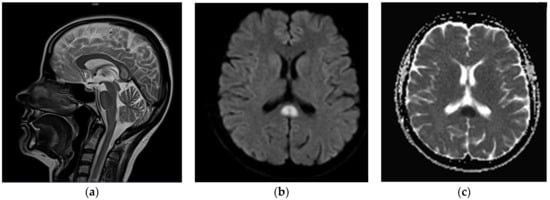

Furthermore, a follow-up MRI with spectroscopy was scheduled in 4–6 weeks to further evaluate the nature and metabolites of the SCC lesion. Consecutive neurological consultation revealed normal neurological status (9 July 2020); the patient did not report episodes of collapse since the previous evaluation. MRI (end of July 2020) indicated substantial regression of the SCC lesion (Figure 3); MR spectroscopy was not performed due to technical reasons (small residual foci). The patient was consulted by a neurosurgeon who did not see any indications for surgical intervention. Only three brief episodes of collapse without loss of consciousness or convulsions were reported by the patient during the consecutive month; minor, occasional concentration deficits were observed as well. A subsequent neurological examination revealed no abnormalities; therefore, treatment with valproic acid at a therapeutic dose of 2 × 300 mg was maintained. The last head MRI (February 2021, 7–8 months after the diagnosis of the lesion) showed complete resolution of the pathological foci within the SCC; there was no change in the appearance of the right parietal meningioma across all consecutive follow-up MR examinations. The neurological status of the patient was normal except for insignificant concentration disorders. Her mood improved markedly. Both the complete clinical image and results of the extensive diagnostic evaluation spoke in favor of a final diagnosis consistent with cytotoxic changes of the corpus callosum (CLOCC) associated with anti-epileptic drug treatment.

Figure 3.

Another follow-up MR examination after 13 months. Substantial regression of the SCC lesion; discrete, indistinct hyperintensity on axial T2w-TIRM (dark fluid) images (a). No signal abnormalities were visible within splenium on other MR sequences—as visible on conventional T2-weighted (blade) sagittal image (b).